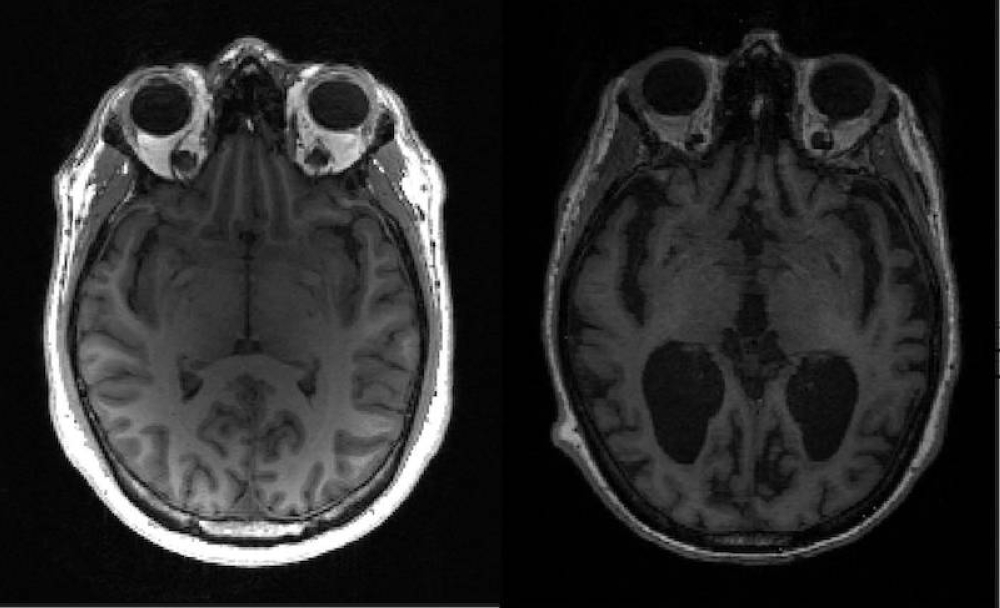

The drug, which is for treating early-stage Alzheimer's and mild cognitive impairment, is a special type of antibody that targets a protein called amyloid beta. The plaque-like protein, which accumulates inside the brain and destroys nerve cells, is considered the cause of the disease.

However, some patients administered the drug experienced side effects like brain edema and bleeding, it said. - BERNAMA